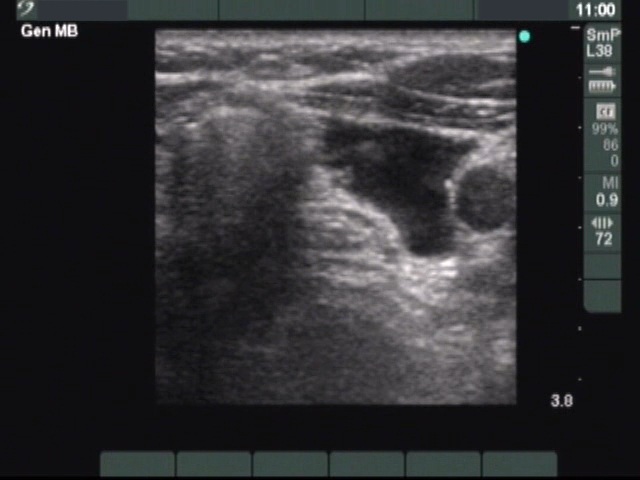

Clinical presentation: a 56-year-old woman with repeatedly aspirated and recurred parathyroid cyst causing complaints. No abnormalities on palpation. The parathormone-level of the cystic fluid was 5 times higher than the upper limit of normal value. Instead of surgical removal, the patient underwent 4 sessions of sclerotherapy.

First row: ultrasonographic picture before sclerotherapy. The size of the lesion was 16x14x32 mm (width x depth x length).